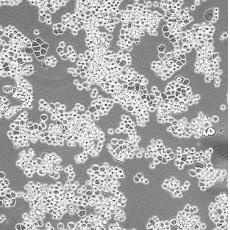

產品名稱 MDA-MB-453

中文名稱 人乳腺癌細胞

組織來源 乳腺腺癌;胸腔積液轉移;女性

生長特性 adherent

形態(tài)特征 epithelial

細胞描述 該細胞系由CailleauR在1976年從一名48歲的患有轉移性乳腺癌的白人女性的心包滲出液中分離建立的。該細胞表達FGF的受體。